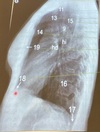

2

3

4

5

Perfectly

Q